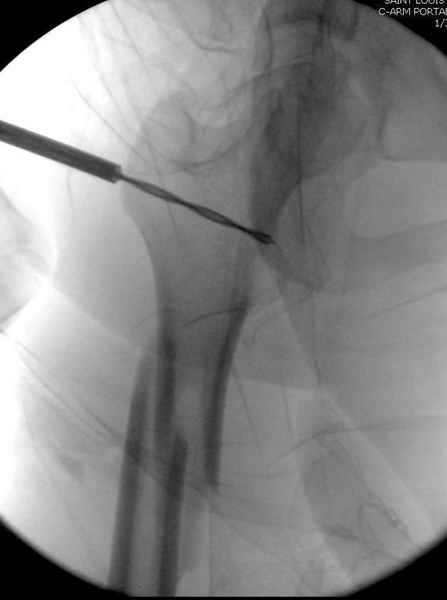

Как раз недавно у меня был примерный случай: больному 36 лет, поступил ночью, травма в результате мотоциклетной аварии, кроме чрезвертельного и спирального перелома левого бедра имеется переломы костей предплечья с этой же стороны. Скелетное вытяжение, а на следующий день больной про оперирован на ортопедическом столе с дистракцией. Чтобы не расколоть чрезвертельный перелом провели временную спицу ближе к переднему кортексу, из малого разреза костодержатель для репозиции, а фиксацию провели антиградным штифтом. Этапы операции на снимках.

DK> Чтобы не расколоть чрезвертельный перелом провели временную спицу

DK> ближе к переднему кортексу,